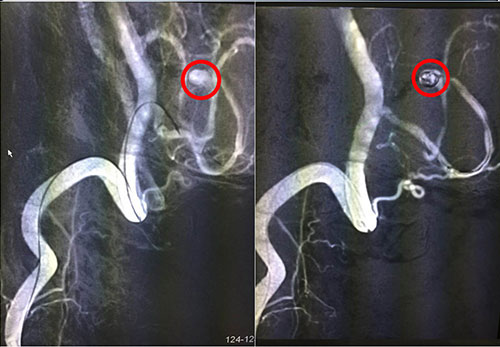

紅圈內(nèi)為術(shù)中介入微導(dǎo)管微彈簧

腦動脈瘤的介入治療,最常用的是用彈簧圈栓塞動脈瘤。簡單地說,就是從大腿根部的股動脈插管,將一根很細(xì)的微導(dǎo)管通過動脈官腔內(nèi)直接插到腦動脈瘤內(nèi),再通過這根很細(xì)的微導(dǎo)管送入一段一段盤旋的微彈簧圈,逐步將動脈瘤腔內(nèi)填滿,誘發(fā)血栓形成后,使動脈瘤腔沒有血流通過,而正常的腦動脈保留通暢,從而達(dá)到治療的目的。12月6日手術(shù)進(jìn)行,術(shù)程順利,患者安返ICU進(jìn)行術(shù)后監(jiān)護(hù)。

我院神經(jīng)外科專家潘仁龍等多次與滬上知名神經(jīng)外科專家聯(lián)合會診,討論患者病情及治療方案,認(rèn)為目前診斷明確,患者病情患者具備手術(shù)指征,手術(shù)方式有:開顱動脈瘤夾閉術(shù)和動脈瘤介入栓塞術(shù)。由于患者左腦后下動脈瘤體在血管遠(yuǎn)端,接近腦干邊上,手術(shù)難度較大,風(fēng)險極大,在術(shù)中、術(shù)后均可能發(fā)生出血而導(dǎo)致死亡可能?紤]到患者情況高危,又開顱動脈瘤夾閉術(shù)相較于介入栓塞術(shù)創(chuàng)傷大,風(fēng)險大,經(jīng)征求家屬意見后,決定為患者全麻下實(shí)施左小腦后下動脈瘤介入栓塞術(shù),由我院神經(jīng)外科專家潘仁龍主任主刀,并特邀華山醫(yī)院專家協(xié)同技術(shù)指導(dǎo)。